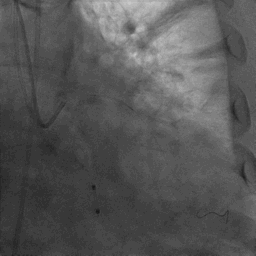

CAG:LAD近中段弥漫钙化,近段80%狭窄,中段90%狭窄,D190%狭窄,中间支近段90%狭窄,右冠近中段弥漫病变,最重狭窄50%。考虑患者胸痛症状可能为冠心病+AS共同作用,以及患者冠脉病变钙化严重,予以旋磨+PCI+TAVR一站式处理。

于中间支植入2.5*18mm支架

1.5mm旋磨头以16万RPM旋磨三次

3.0*15mm球囊后扩张

3.0*15mm球囊预处理LAD近段病变

复查冠脉造影结果满意

造影提示微少量返流,压力监测提示主动脉瓣压差7mmHg